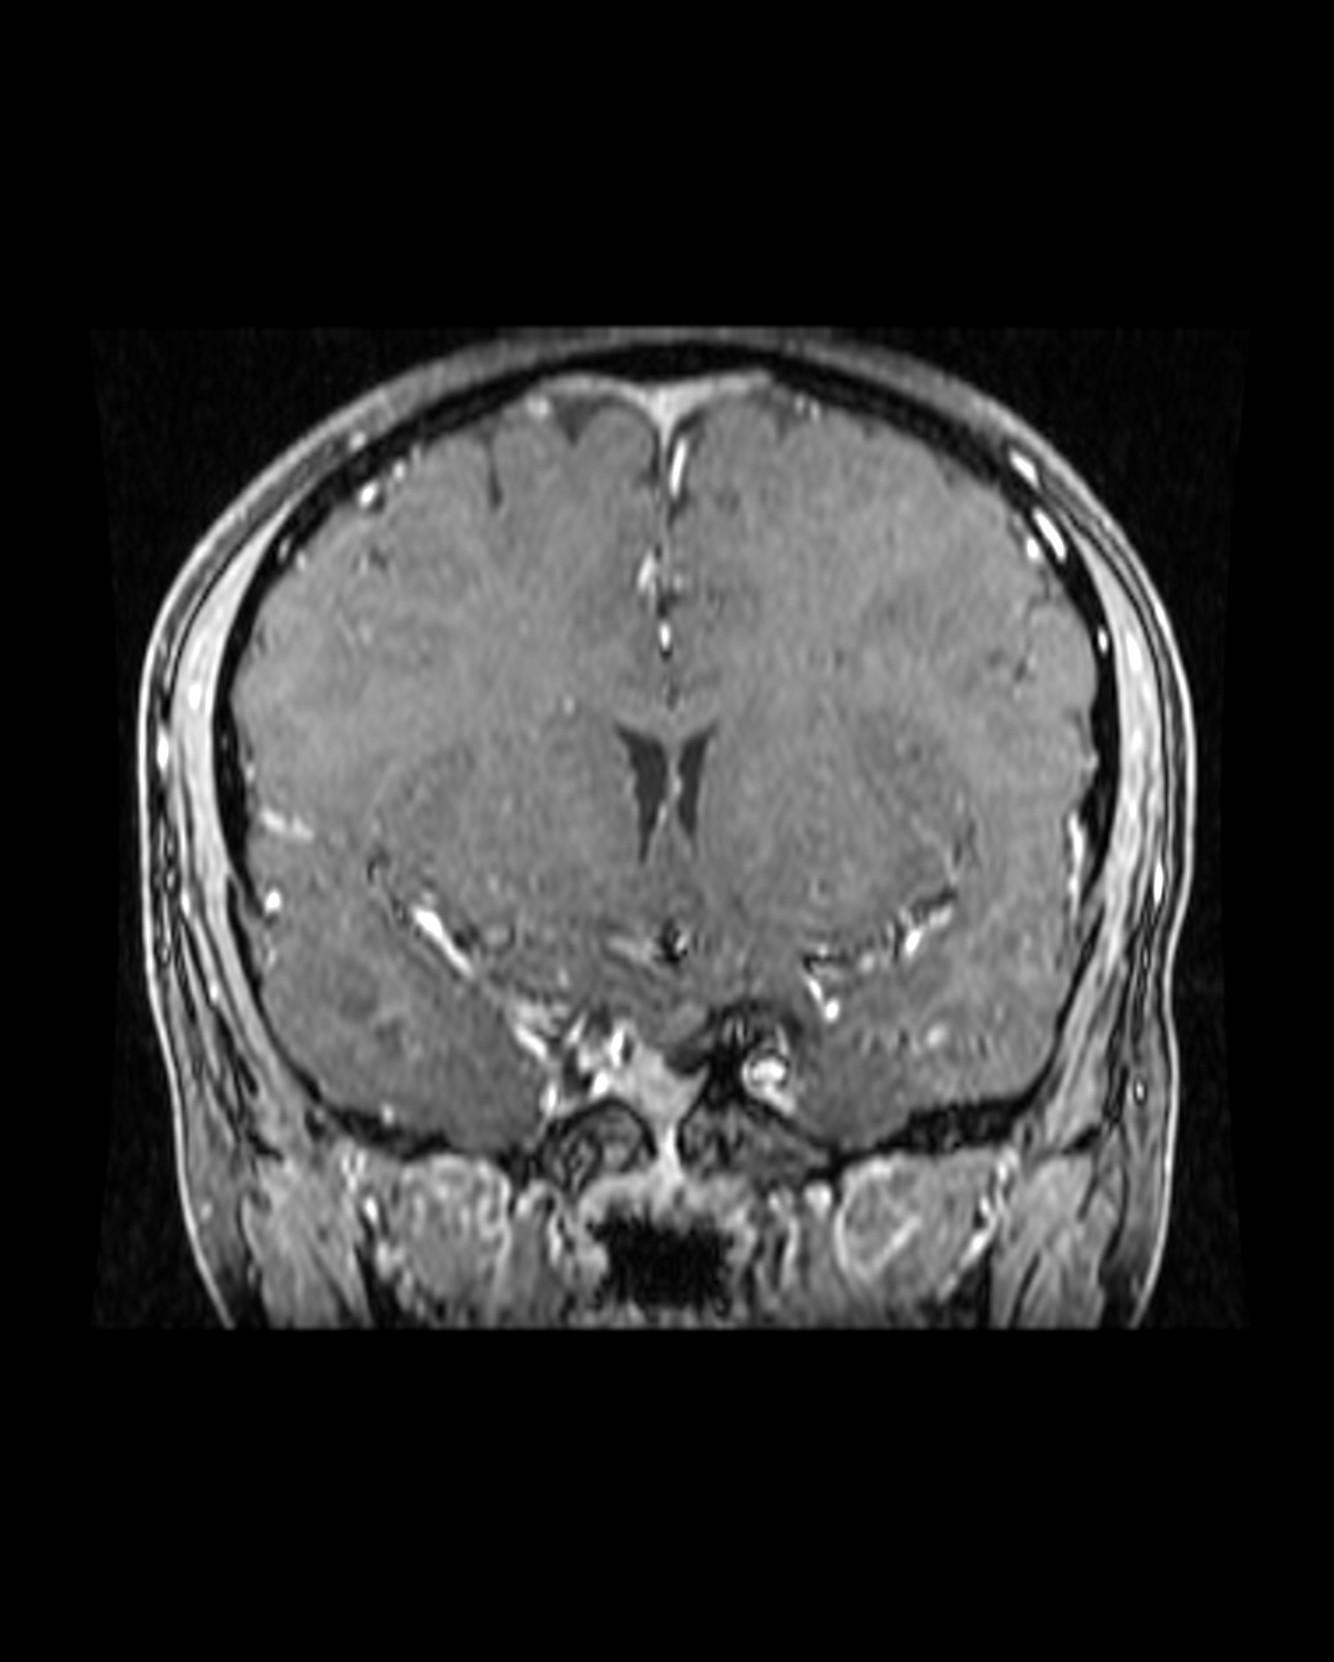

Figure 2: Medial sphenoid wing meningiomas can present different set of technical challenges based on their involvement of the medial neurovascular structures and the encasement of the carotid artery’s perforating vessels. A medial sphenoid wing meningioma with minimal medial extension is shown (upper images). The Sylvian middle cerebral artery branches drape over the superior pole of the tumor. A more true medial sphenoid wing/clinoidal meningioma with significant medial extension and encasement of the ICA is also included (lower images).